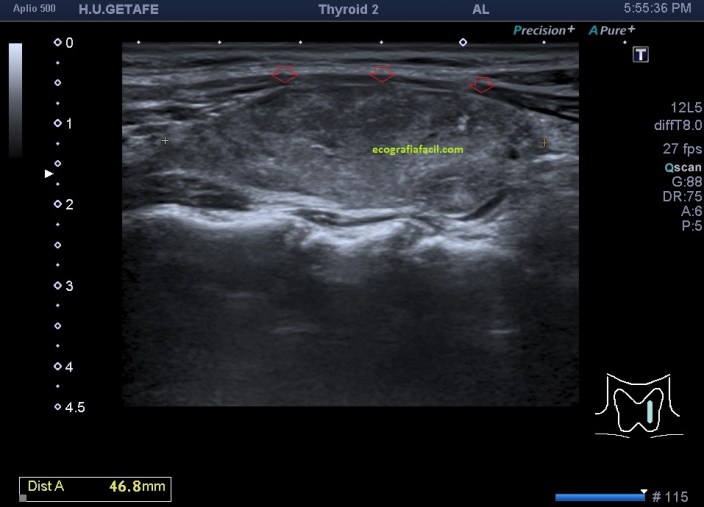

Lo primero, reconoce siempre la normalidad para poder identificar anormalidad. En la imagen 1 tienes una imagen normal de ambos lóbulos tioideos en un corte axial (nos sirve para repasar anatomía básica), en la imagen 2 un corte longitudinal de uno de los lóbulos con su vascularización típica. Bien guarda en tu cabecita estas dos imágenes y ponte en modo concentración para descubrir los cambios semiológicos en el caso de la paciente referida con anterioridad.

En la imagen 3, el corte axial de ambos lóbulos tiroideos afectados. Compara imagen 1 e imagen 3 y te vas a dar cuenta como a veces, en el primer segundo la exploración ya sabes que la glándula es patológica, como es la imagen 3.